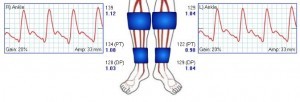

Testing for Purple Feet with Ankle Brachial Index

A Common concern for patients who have purple feet is whether they have poor circulation. And by the term ‘circulation’ they mean artery flow. This is actually uncommon. For arterial blockages to cause color changes, they need to be severe. But in reality, most patients will not have critical limb ischemia. In fact, color changes are much more typical of constricted arteries or of blood pooling in dilated arteries. But still, sometimes ruling our artery blockages makes sense (or you just do it to address the patient’s anxiety). If that is the case, the first screening test will be the ankle brachial index. More comprehensive information is available with pulse volume recordings. Both of these tests will be able to show if there is reduced artery blood flow to the feet. They will usually not be enough to show where the blockage is or if fixing it is possible. But they are good for screening purposes.

Even more information can be obtained with the toe brachial index and with toe-wave tracings. These are also known as photoplathysmographic tracings or PPG’s. The PPG’s can be repeated at room temperatures and with heating or cooling. If there is change you can diagnose artery constriction with temperature. This may lead to a diagnosis of acrocyanosis, Raynaud’s or similar condition. If the waveforms are abnormal, but do not respond to temperature changes, you should look for specific reasons. Practically, you can order pulse volume recordings and toe waveform tracings at the same time.